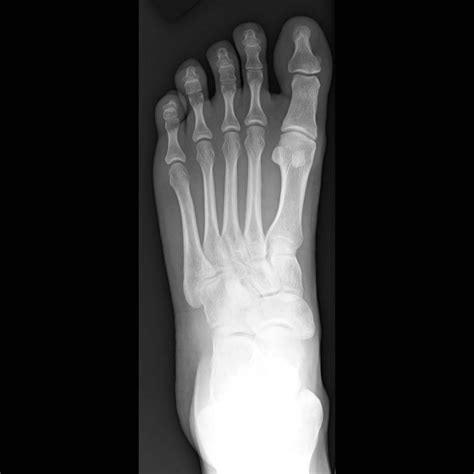

Are you ready to take a peek at your foot's secrets? Well, you're in for a treat as we examine foot x-ray images. Don't worry; it's not as scary as it sounds. In fact, it's quite fascinating! You'll be surprised at what you can learn about your feet just by looking at an x-ray image. So, let's dive in and explore the world of foot anatomy!Firstly, we must understand why doctors use foot x-rays. It's not just to satisfy their curiosity, but it's also to diagnose any problems or injuries affecting your feet. Foot x-rays help doctors identify fractures, arthritis, bone spurs, and other abnormalities that may be causing pain or discomfort. So, if you've been experiencing any foot-related issues, a foot x-ray might be in order.Now, let's talk about what you can expect during a foot x-ray. Firstly, you'll be asked to remove any jewelry or metal objects from your feet as it can interfere with the imaging process. Then, you'll place your foot on a special platform while the x-ray machine takes pictures. It's completely painless and usually takes only a few minutes. Once the images are taken, your doctor will analyze them and determine if any further action is needed.One thing you'll notice when looking at a foot x-ray image is the intricate network of bones. The human foot has 26 bones, and each one has a specific purpose in supporting our weight and enabling us to walk, run, and jump. It's amazing how these tiny bones work together to provide stability and flexibility to our feet.Another interesting aspect of foot x-rays is the differences between left and right feet. Did you know that no two feet are exactly alike? Even your left and right foot have subtle differences in size and shape. These differences can be seen in x-ray images, which help doctors make accurate diagnoses and prescribe the right treatment.Of course, foot x-rays are not just limited to humans. Veterinarians also use x-rays on animals, particularly horses. Horse owners often get foot x-rays for their animals to diagnose lameness and other foot-related issues. It's amazing how the same principles apply to both humans and animals.In conclusion, foot x-ray images may seem like a mundane medical procedure, but they offer a fascinating glimpse into the complexity of our feet. From bones to joints to ligaments, there's so much to learn from a simple x-ray image. So, the next time you're at the doctor's office, don't be afraid to ask for a foot x-ray. Who knows what secrets your feet might be hiding!

Speaking of bone visibility, foot xrays are a veritable feast for the eyes (if you're into that sort of thing). There are 26 bones in the human foot, and they all show up beautifully on an xray image. From the delicate phalanges to the sturdy metatarsals, each bone is unique and fascinating in its own way.

Of course, bones aren't the only things that show up on a foot xray. Joints play a big role as well, and there are plenty of them in the foot. Whether you're admiring the smooth surfaces of the ankle joint or marveling at the intricacy of the midfoot joints, there's no denying that foot xrays offer a fascinating glimpse into the inner workings of our bodies.